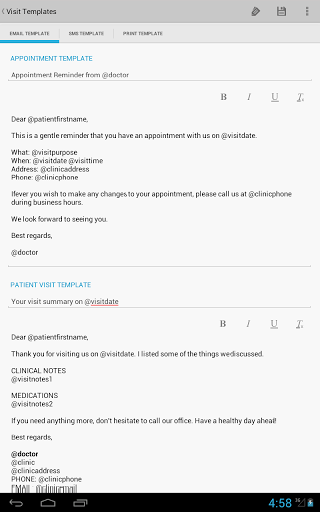

• Envoyer un rappel de rendez-vous médical au patient par courriel ou par SMS

• Envoyer le résumé de la visite au patient par email ou SMS

• Modèles de courrier électronique et de SMS personnalisables